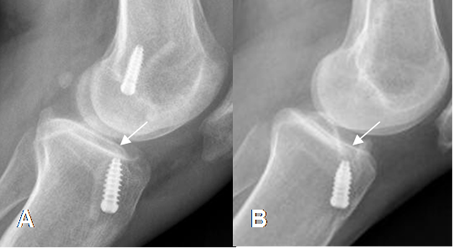

Fig 135. Mala orientación del túnel tibial.

A: Rx lateral de rodilla y B: RM sagital en T2. Túnel muy anterior, localizado en la parte inicial de la tibia.